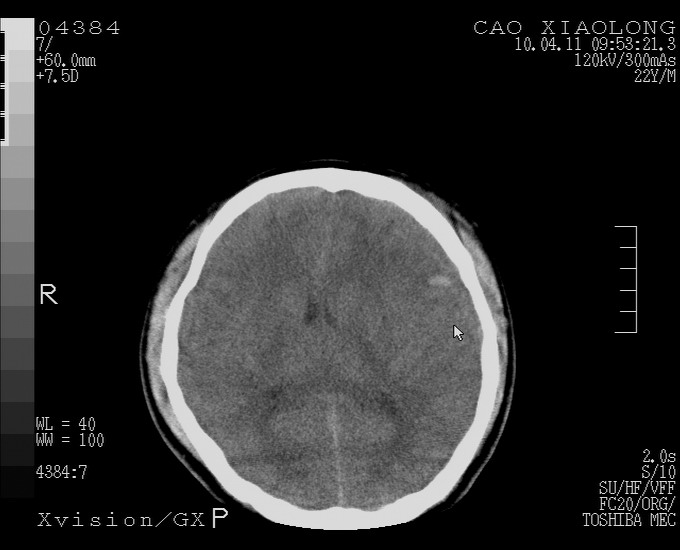

以下是引用随光逐影在2010-4-11 11:00:00的发言:[br]1)左侧额颞顶部硬膜下血肿。2)蛛网膜下腔出血。3)右侧颞顶部颅骨线形骨折。[br][br]20小时后复查:左侧额颞叶脑挫裂伤;左侧额颞顶部硬膜下血肿及蛛网膜下腔出血有吸收表现;右侧颞顶部颅骨线形骨折。[br]